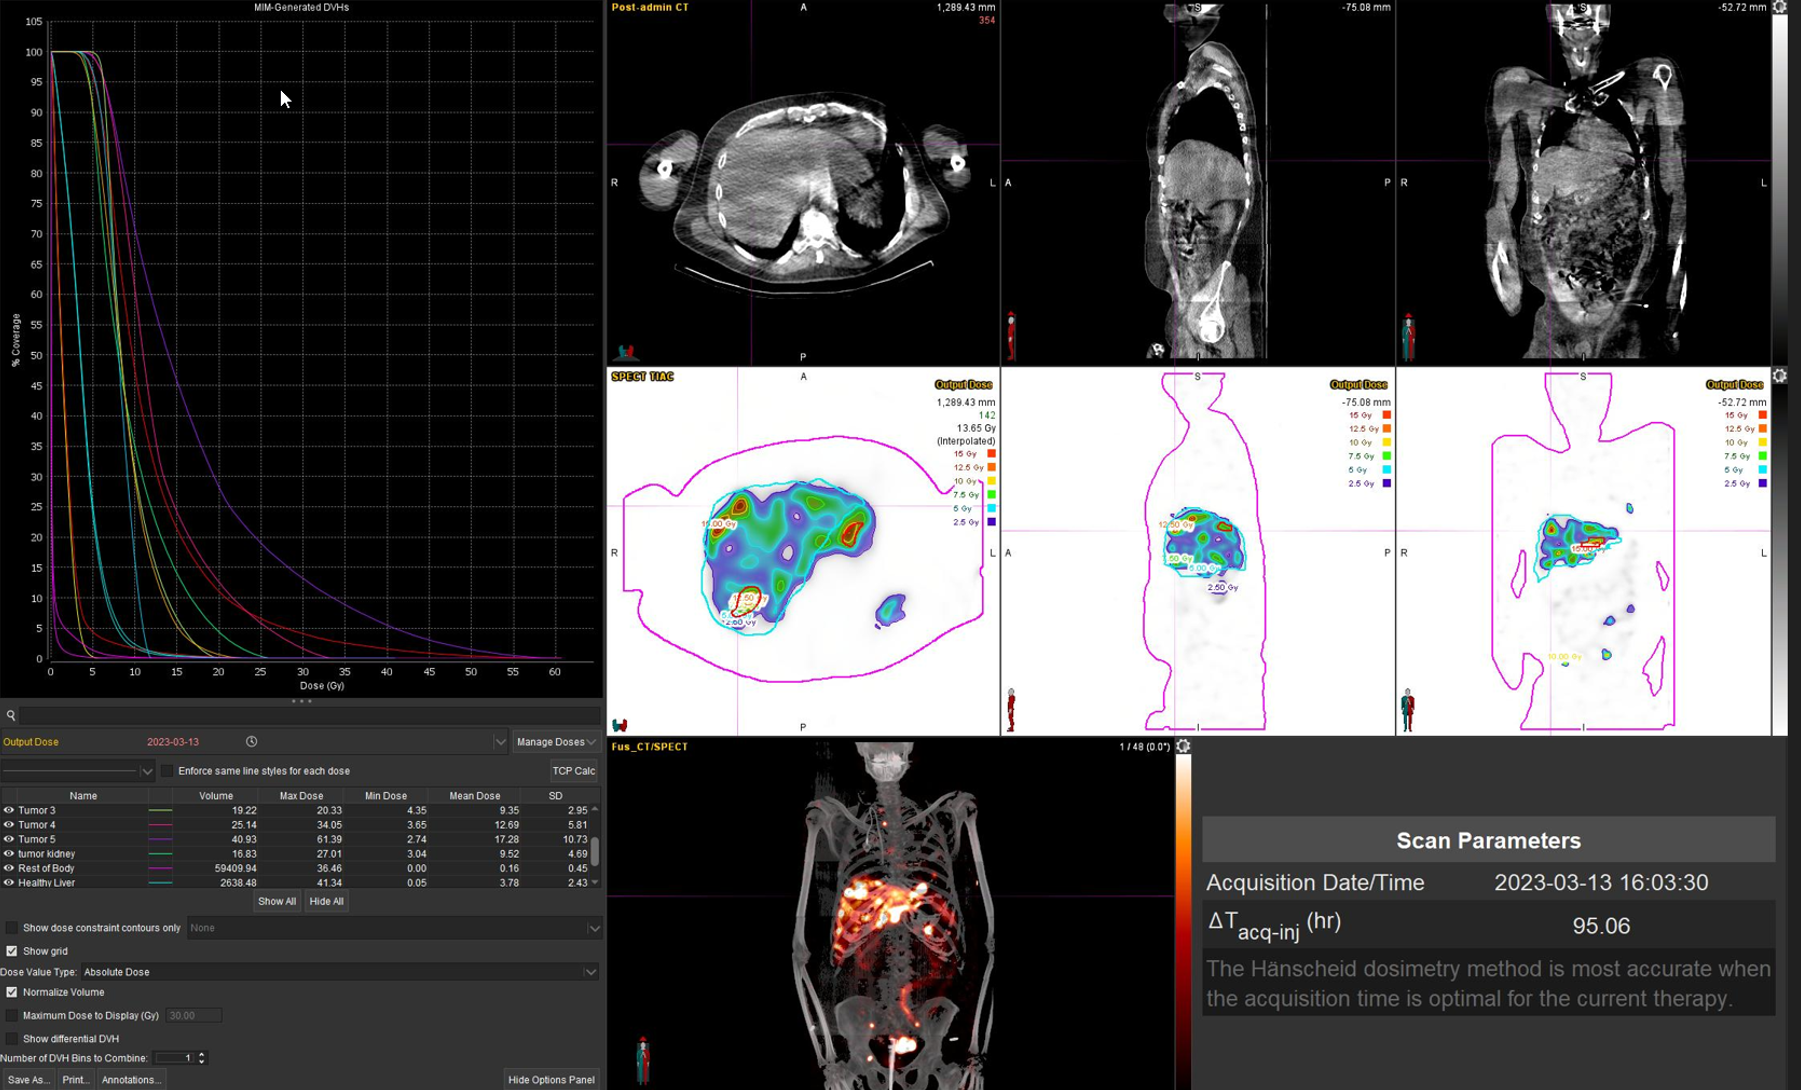

Η θεραπεία με Ύτριο-90 SIR-Spheres (Y-90) αποτελεί μια εξειδικευμένη τεχνική εκλεκτικού ενδοαρτηριακού εμβολισμού, η οποία στοχεύει αποκλειστικά τον όγκο μέσω των ηπατικών αγγείων, επιτρέποντας την εναπόθεση σωματιδίων που εκπέμπουν ραδιενέργεια τοπικά με ελάχιστη ακτινική επιβάρυνση στους υγιείς ιστούς. Η διαδικασία περιλαμβάνει λεπτομερή προθεραπευτικό αγγειογραφικό σχεδιασμό με αξιολόγηση της αγγειακής ανατομίας και χορήγηση ενός ιχνηθέτη για την ανίχνευση τυχόν διαφυγής (πχ. lung shunt), εξασφαλίζοντας μέγιστη ασφάλεια και εξατομίκευση. Η επιλογή της δόσης γίνεται πλέον με σύγχρονα υπολογιστικά μοντέλα δοσιμετρίας και εξειδικευμένα λογισμικά (όπως MIM ή SIR-TeX platform), τα οποία επιτρέπουν ακριβή αποτύπωση του όγκου της νόσου στο ήπαρ, υπολογισμό του πραγματικού tumor burden και εκτίμηση της απορροφούμενης δόσης τόσο στον όγκο όσο και στο υγιές ηπατικό παρέγχυμα. Μετά τη θεραπεία, πραγματοποιείται έλεγχος κατανομής της ακτινοβολίας (μέσω Bremsstrahlung SPECT/CT ή PET/CT), ενώ ακολουθεί στενή απεικονιστική και κλινική παρακολούθηση για την αξιολόγηση της ανταπόκρισης, την εκτίμηση τυχόν τοξικοτήτων και τον σχεδιασμό επόμενων βημάτων στην ογκολογική στρατηγική του ασθενούς. Πρόκειται για μια ιδιαίτερα αποτελεσματική θεραπευτική επιλογή σε πρωτοπαθείς ηπατικούς όγκους και σε ηπατικές μεταστάσεις, ειδικά όταν οι συμβατικές θεραπείες έχουν περιορισμένη αποτελεσματικότητα ή δεν είναι πλέον εφικτές.

Η θεραπεία με Lu-177 DOTATATE (PRRT – Peptide Receptor Radionuclide Therapy) αποτελεί μια από τις πλέον εξελιγμένες μορφές στοχευμένης ραδιονουκλιδικής θεραπείας για νευροενδοκρινείς όγκους του γαστρεντερικού και του παγκρέατος, αξιοποιώντας την υπερέκφραση των υποδοχέων σωματοστατίνης στους νεοπλασματικούς ιστούς. Η διαδικασία περιλαμβάνει τον ακριβή προσδιορισμό της έκτασης της νόσου μέσω Ga68 DOTATATE PET/CT, την επιβεβαίωση υψηλής έκφρασης υποδοχέων SSTR και στη συνέχεια τη χορήγηση του Λουτέσιο-177 DOTATATE, το οποίο δεσμεύεται εκλεκτικά στους ανωτέρω υποδοχείς. Η ενέργεια του β-εκπομπού Λουτέσιου επιτρέπει στοχευμένη κυτταροτοξική δράση μέσα στον όγκο, με ελάχιστη διασπορά σε υγιείς ιστούς. Η σύγχρονη πρακτική ενσωματώνει ειδικά λογισμικά δοσιμετρίας, που υπολογίζουν την απορροφούμενη δόση σε κρίσιμα όργανα (ήπαρ, νεφροί, μυελός) και την πραγματική δόση στον όγκο, επιτρέποντας εξατομικευμένο σχεδιασμό και βελτιστοποιημένη θεραπευτική στρατηγική. Μετά από κάθε κύκλο θεραπείας πραγματοποιείται απεικονιστικός έλεγχος, αξιολόγηση τοξικοτήτων και συνολική εκτίμηση ανταπόκρισης, καθοδηγώντας τις επόμενες φάσεις της θεραπείας. Το Lu-177 DOTATATE έχει αποδειχθεί εξαιρετικά αποτελεσματικό στη σταθεροποίηση και συχνά στη συρρίκνωση της νόσου, παρατείνοντας την επιβίωση και βελτιώνοντας σημαντικά την ποιότητα ζωής των ασθενών.

Η αξία της μεταθεραπευτικής δοσιμετρίας

Με τη SPECT‑CT ποσοτικοποίηση υπολογίζουμε απορροφούμενες δόσεις σε όγκους και όργανα‑στόχους (νεφροί, σιελογόνοι, ήπαρ, μυελός κ.ά.). Αυτό:

Σημείωση: Σύμφωνα με πρόσφατες κλινικές εργασίες/σειρές ασθενών – όπως οι LUMEN‑2 (για ΝΕΤ) και νεότερες μελέτες σε PSMA‑στόχο – η ποσοτική δοσιμετρία συσχετίζεται με την έκβαση και βελτιώνει τον θεραπευτικό σχεδιασμό.